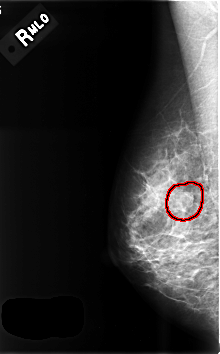

C_0507_1.LEFT_CC

FILE: C_0507_1.LEFT_CC.OVERLAY

TOTAL_ABNORMALITIES 1

ABNORMALITY 1

LESION_TYPE MASS SHAPE LOBULATED MARGINS CIRCUMSCRIBED

ASSESSMENT 3

SUBTLETY 5

PATHOLOGY BENIGN

TOTAL_OUTLINES 1

BOUNDARY